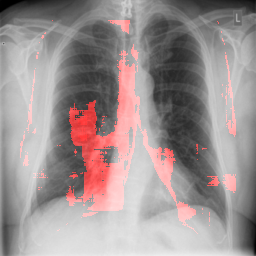

4.2.2 Pulmonary Edema Localization

In order to test the effectiveness of the localization procedure in areas other than the heart region, we chose pulmonary edema which occurs in the lung region. Also, pulmonary edema is detected by the net like white structure in the lung area. No anatomical shape change is associated with the abnormality. We have found that the localization is obtained best when the ROIs of lungs are taken to compute the map. Following the scheme in section 3.4, localization experiment on pulmonary edema is performed as shown in Fig. 8. It has been observed that the classifier is not sensitive to the fine features like septal or Kerley B lines. The localization is mainly obtained in the lung region where excess fluid is observed. Some localization regions are outside the lung region which occurs primarily for the fact that, even though the occlusion center is outside the lung, it occludes lung region and thus the probability drop occurs.

In a similar fashion, additional localization results for Pulmonary Edema is shown in Fig. 13. In Fig. 13(a) and (b) localization of two examples of CXRs with Pulmonary Edema is shown. As stated earlier the classifier localizes in the lung region. This is not the case when normal images are used to localize Pulmonary Edema as seen in Fig. 13(c) and (d). The localizations are obtained in random dense locations such as the sternum or heart. Like the cardiomegaly case, the histogram averages for CXRs with pulmonary Edema (Fig. 13(e)) shows a sensitivity toward pulmonary edema detection while the normal CXRs shows a spread out detection. It is interesting to note that, in the histogram of normal images high probability (¿0.85) is non-existent, thus ensuring low false positive rate. In the test set none of the normal images have been diagnosed as Pulmonary Edema. The failure cases are shown in Fig. 12. These CXRs are with Pulmonary Edema. However, the localization algorithm shows that one of them localizes in lungs whereas the other one shows a localization pattern similar to that obtained in normal CXRs.